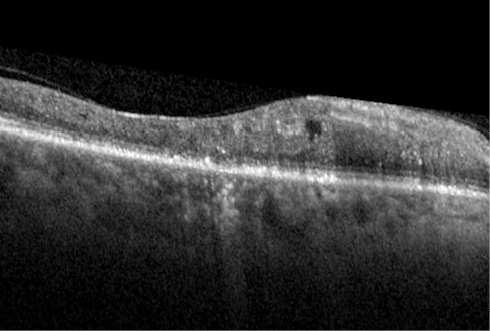

Figure 1. After treatment for radiation retinopathy, the CRT of this patient’s eye remained at 510 μm.

In November 2009, the patient underwent focal laser treatment in her right eye. Fluorescein angiography at this time showed florid macular edema. She subsequently received two additional bevacizumab injections over the next 2 months, but her vision never demonstrated improvement. By August 2010, her central retinal thickness (CRT) was 510 μm (Figure 1). She was again treated with focal laser and bevacizumab. Her CRT showed minimal improvement, remaining in the mid to high 400-μm range.